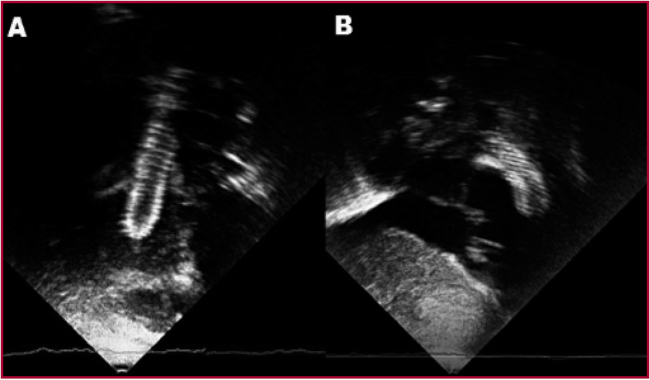

Las imágenes del SNC de ambos pacientes no evidenciaron signos de isquemia ni sangrado significativos. Luego del alta hospitalaria todos los pacientes fueron seguidos regularmente por su cardiólogo de cabecera con controles clínicos que incluyeron registro de saturación periférica de oxígeno, electrocardiograma de 12 derivaciones, telerradiografías de tórax y ecocardiograma Doppler color (Figura 4). Previo a la corrección quirúrgica completa, se indicó cateterismo cardíaco para valorar el tracto de salida, el stent implantado y el crecimiento de las ramas pulmonares.

Imágenes de ecocardiografía Doppler color en eje subcostal (A) largo y (B) corto, mostrando el stent implantado en el tracto de salida del ventrículo derecho.